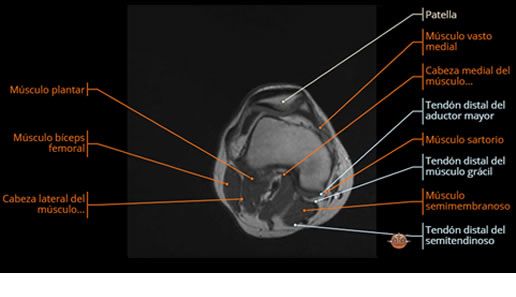

Se realiza estudio de MRI de muslo izquierdo en diferentes planos, con secuencias de Spin Echo, GRE; ponderadas a T1 y a T2, se utilizan pulsos de saturación de grasa y se administra medio de contraste IV a base de Gadolinio en base al peso del paciente.

La diáfisis femoral izquierda muestra reacción perióstica importante, se extiende desde el cuello del fémur, invade trocánteres, diáfisis femoral, medial y distal, es compatible con un proceso infeccioso óseo, el complejo muscular del muslo se ve edematizado.

Hallazgos en Resonancia Magnética (RM)

La resonancia es la modalidad de elección para valorar la extensión intramedular y la infiltración en tejidos blandos, brindando una imagen más detallada del compromiso tumoral. Los hallazgos característicos incluyen:

Lesión de señal heterogénea en secuencias T1 (hipointensa) y T2/STIR (hiperintensa), que refleja necrosis, hemorragia y contenido celular diverso.

Realce intenso y heterogéneo tras la administración de contraste (gadolino), lo que indica vascularización tumoral.

Compromiso de la médula ósea adyacente y de estructuras vecinas, como músculos y neurovasculatura.

Posible presencia de edema óseo y necrosis central.